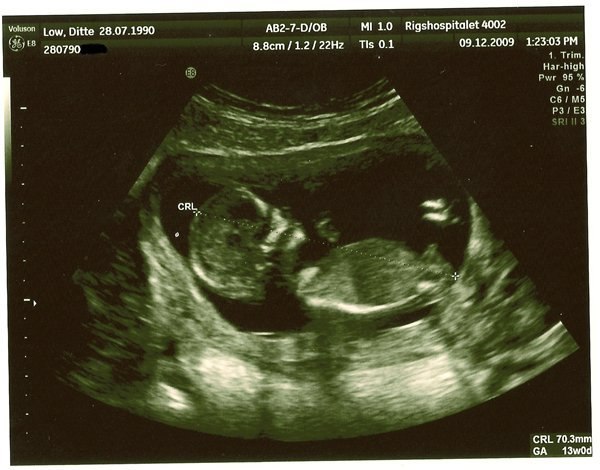

Min søn fra 4+3 til nu :)

Jeg har lige lyst til at vise lidt her fra . Jeg synes det er gået meget hurtigt faktisk. Når jeg tænker på lige da jeg fandt ud af at jeg var gravid til at han er 6½ måned nu . Mors store dreng! Der er bare sket så mange ting de sidste 2 år ca, ting jeg IKKE fortryder på noget tidspunkt .

Vedhæftede fotos (klik for at se i fuld størrelse)